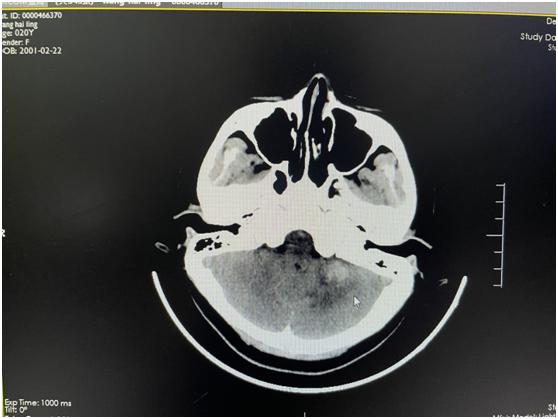

該患者因“突發(fā)頭痛、頭暈伴惡心嘔吐3天”入院,發(fā)病時就診當?shù)蒯t(yī)院,行頭顱CT顯示左側(cè)小腦出血,后轉(zhuǎn)我院進一步治療。在我院完善頭顱磁共振后考慮血管性疾病出血,給予全腦血管造影顯示左側(cè)小腦動靜脈畸形?;颊邽槟贻p女性,結(jié)合病情,家屬要求選擇創(chuàng)傷小、無手術(shù)疤痕的介入治療。神經(jīng)外科團隊積極完善術(shù)前準備,認真閱讀全腦血管造影圖像后制定了嚴密的手術(shù)方案。術(shù)中,科室團隊在傳統(tǒng)介入手法進行操作的基礎(chǔ)上,同時建立動脈及靜脈通道,動脈栓塞時因栓塞劑返流嚴重,立即采用備用方案經(jīng)靜脈途徑,由畸形團出口處反向注入栓塞材料,畸形團栓塞效果確切,完全未顯影,供血動脈及引流靜脈完好,基本達治愈效果?;颊咝g(shù)后神志清楚,無顱神經(jīng)受損癥狀,四肢活動正常,術(shù)后5天痊愈出院。

圖1:CT提示左側(cè)小腦出血